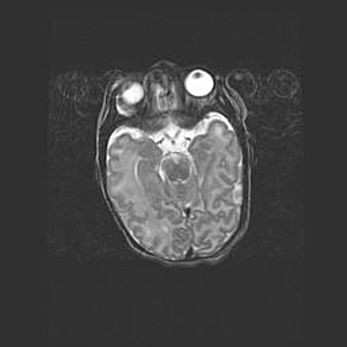

Лейкомаляция с кистозно-глиозной дегенерацией головного мозга.

Возраст: 2 месяца 25 дней

Вес: 6400 г

Окружность головы: 40 см

Срок гестации: 41 неделя

Лейкомаляцию относят к ишемически-гипоксическим повреждениям головного мозга, диагностируемым у новорожденных. При лейкомаляции в головном мозге обнаруживают очаги некроза, возникшие после тяжелой гипоксии и нарушения кровотока. В процессе морфогенеза очаги проходят три стадии: 1) развития некроза, 2) резорбции и 3) формирования глиозного рубца или кисты. Перивентрикулярная лейкомаляция (ПЛ) встречается примерно в 12% случаев среди новорожденных, обычно – у недоношенных детей, причем, частота ее зависит от массы, с которой младенец появился на свет. Наибольшее число малышей страдает лейкомаляцией, если масса при рождении 1500-2500 г.